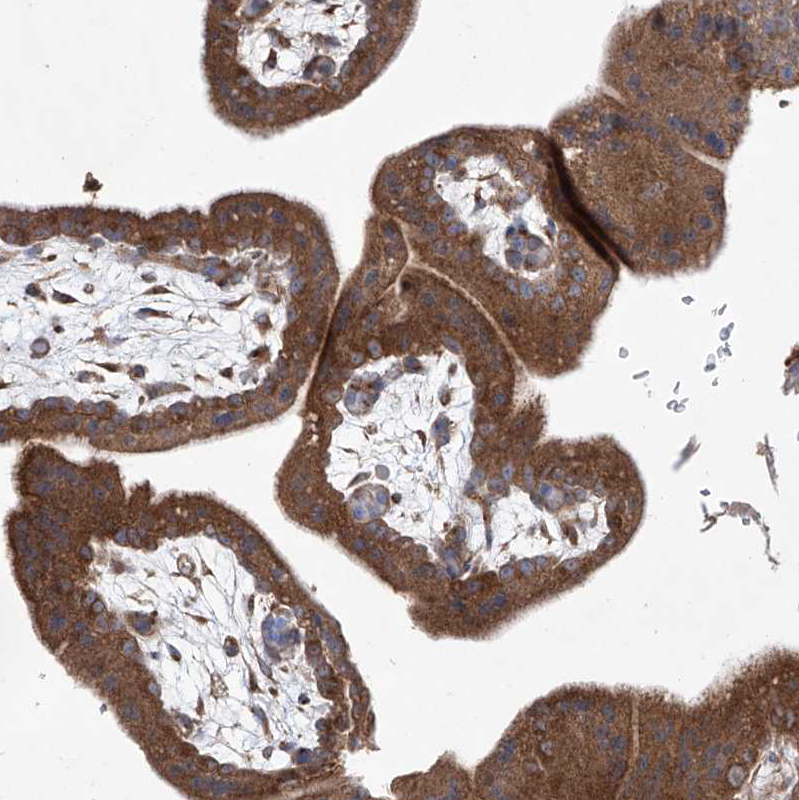

Immunohistochemistry analysis in human duodenum and tonsil tissues using HPA030169 antibody. Corresponding KLC4 RNA-seq data are presented for the same tissues.